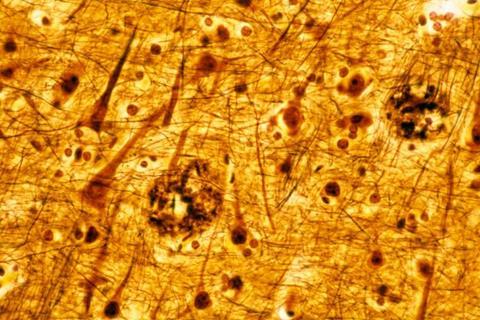

The new agreement between Bristol Myers Squibb and BioArctic is set to advance development of anti-amyloid-beta antibody treatments, which have shown symptomatic benefit in Alzheimer's.